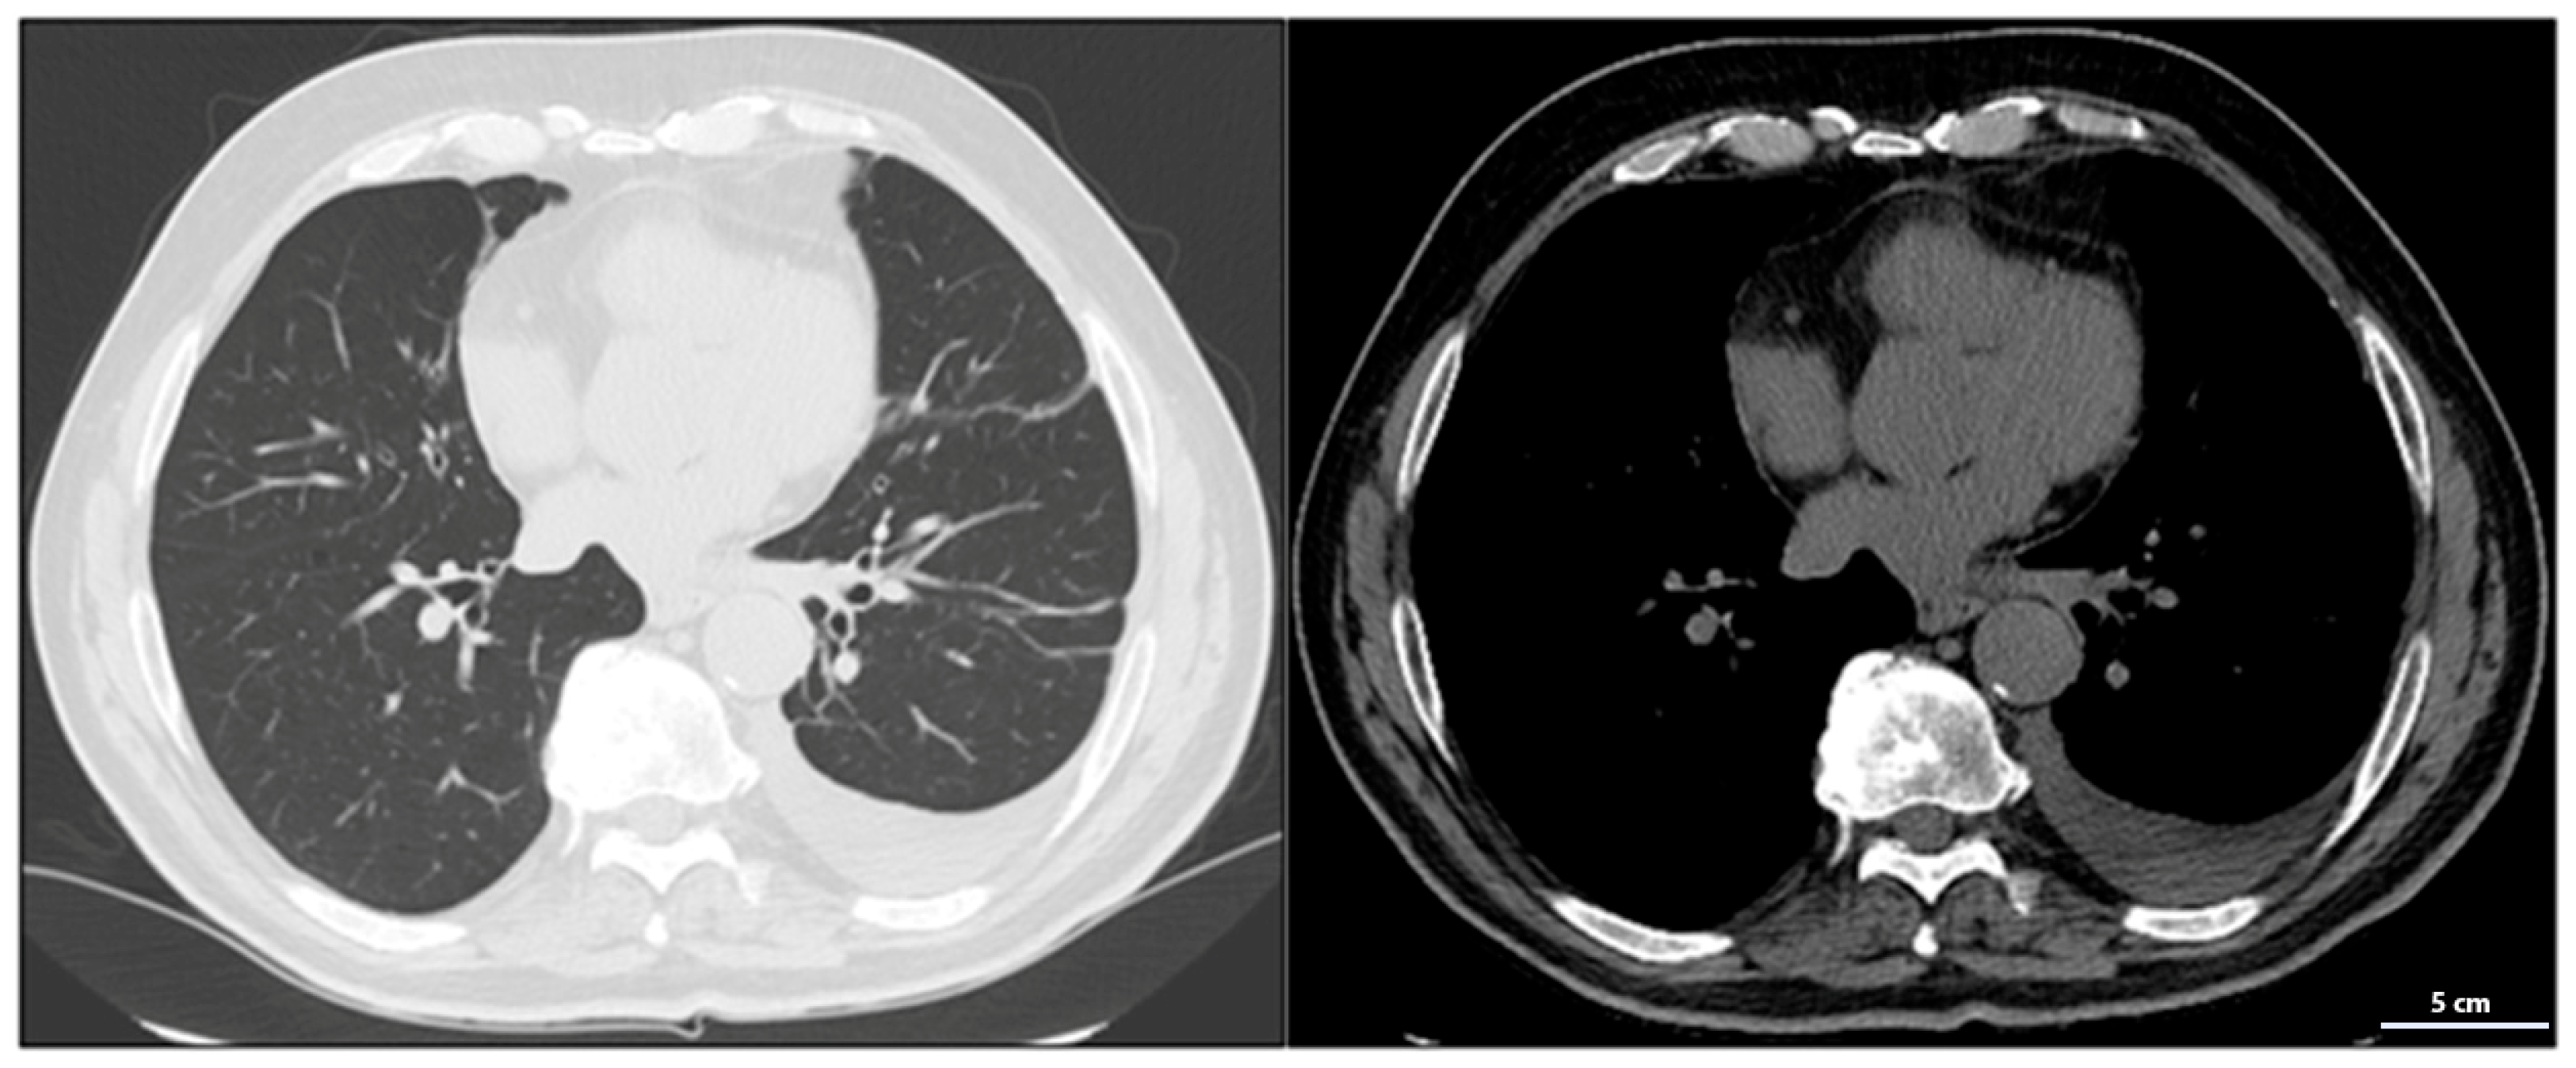

The October 2023 CT scan confirmed the absence of disease progression, with further stabilization of the mediastinal and lateral cervical lymph nodes, now measuring <1 cm and no longer clinically significant, indicating good disease control.

By March 2024, CT imaging showed further improvement, with a reduction in mediastinal lymph node size to 7 mm in the aorto-pulmonary window and 11 mm at the right hilum. No new pulmonary or nodal lesions were observed, confirming continued disease control without signs of progression.

At the radiological follow-up in July 2024, imaging demonstrated sustained disease stability, with no new pleural effusions and stable lymph nodes. These findings confirmed a prolonged response to atezolizumab, representing a rare case of long-term disease control in advanced-stage small-cell lung cancer (SCLC), with some lymph nodes completely resolving and others reduced to clinically insignificant sizes. At the most recent radiological follow-up performed on 10 March 2025, total-body CT imaging confirmed continued disease stability. No evidence of recurrence was observed in the thoracic region, and there were no new lesions detected either in the lungs or at extra-pulmonary sites. This further supports the sustained response to maintenance immunotherapy with atezolizumab.

Serial CT and PET-CT scans over a 24-months period confirmed the absence of new lesions and sustained tumor control. Lymph node involvement, initially extensive, showed significant regression, with some nodes completely resolving. This case suggests that, in select patients, chemo-immunotherapy may induce durable responses beyond standard expectations, warranting further investigation into predictive biomarkers (Figure 5 and Figure S3).

Figure 5.

Reduction of mediastinal lymphadenopathy during treatment with combination therapy and maintenance with atezolizumab.